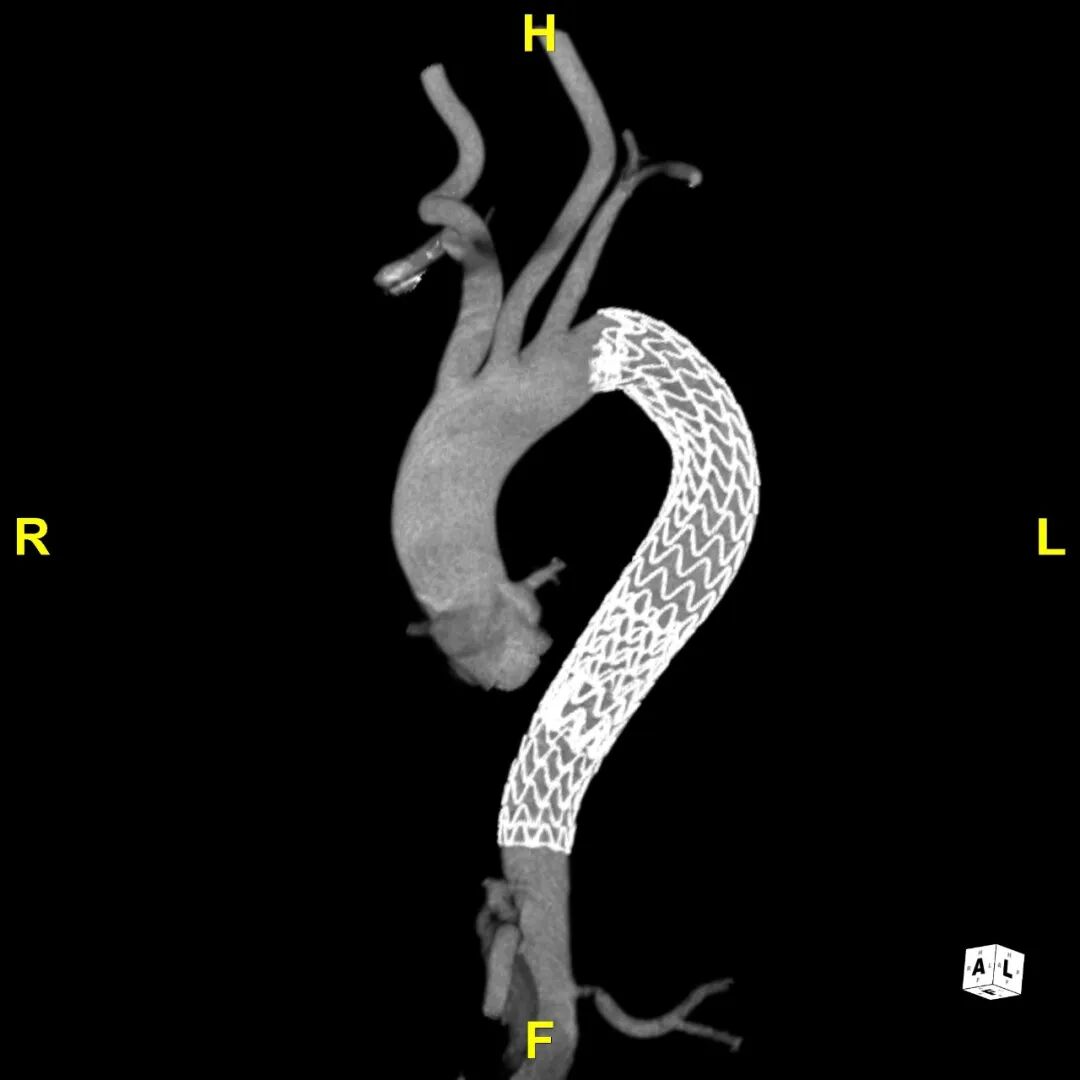

患者出院前进行CTA复查,支架形态良好,与血管壁紧密贴合无内漏,胸主段假腔隔绝,真腔重塑良好。

术后CTA

术后3D重建动态

术后3D重建